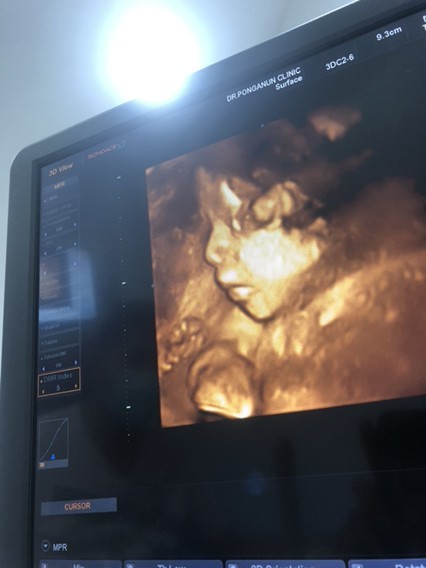

29 สัปดาห์แล้ว กับลูกชายคนแรก แม่ตื่นเต้นมากค่ะ อยากเจอลูกแล้ว 💓🤰

Post reply image